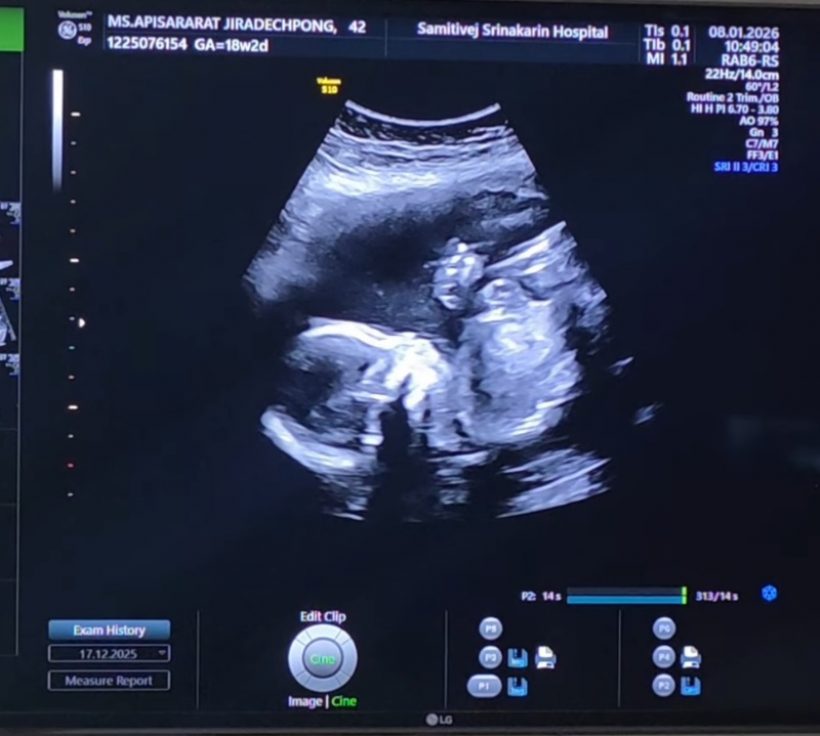

ล่าสุด ลีซอ โพสต์อินสตราแกรม @leesawls14 เผยโมเมนต์อัลตร้าซาวด์ลูกน้อยในครรภ์ภรรยา พร้อมแคปชั่นระบุว่า "รอวันพบกันนะลูกนะ #18w2d #LFbaby"